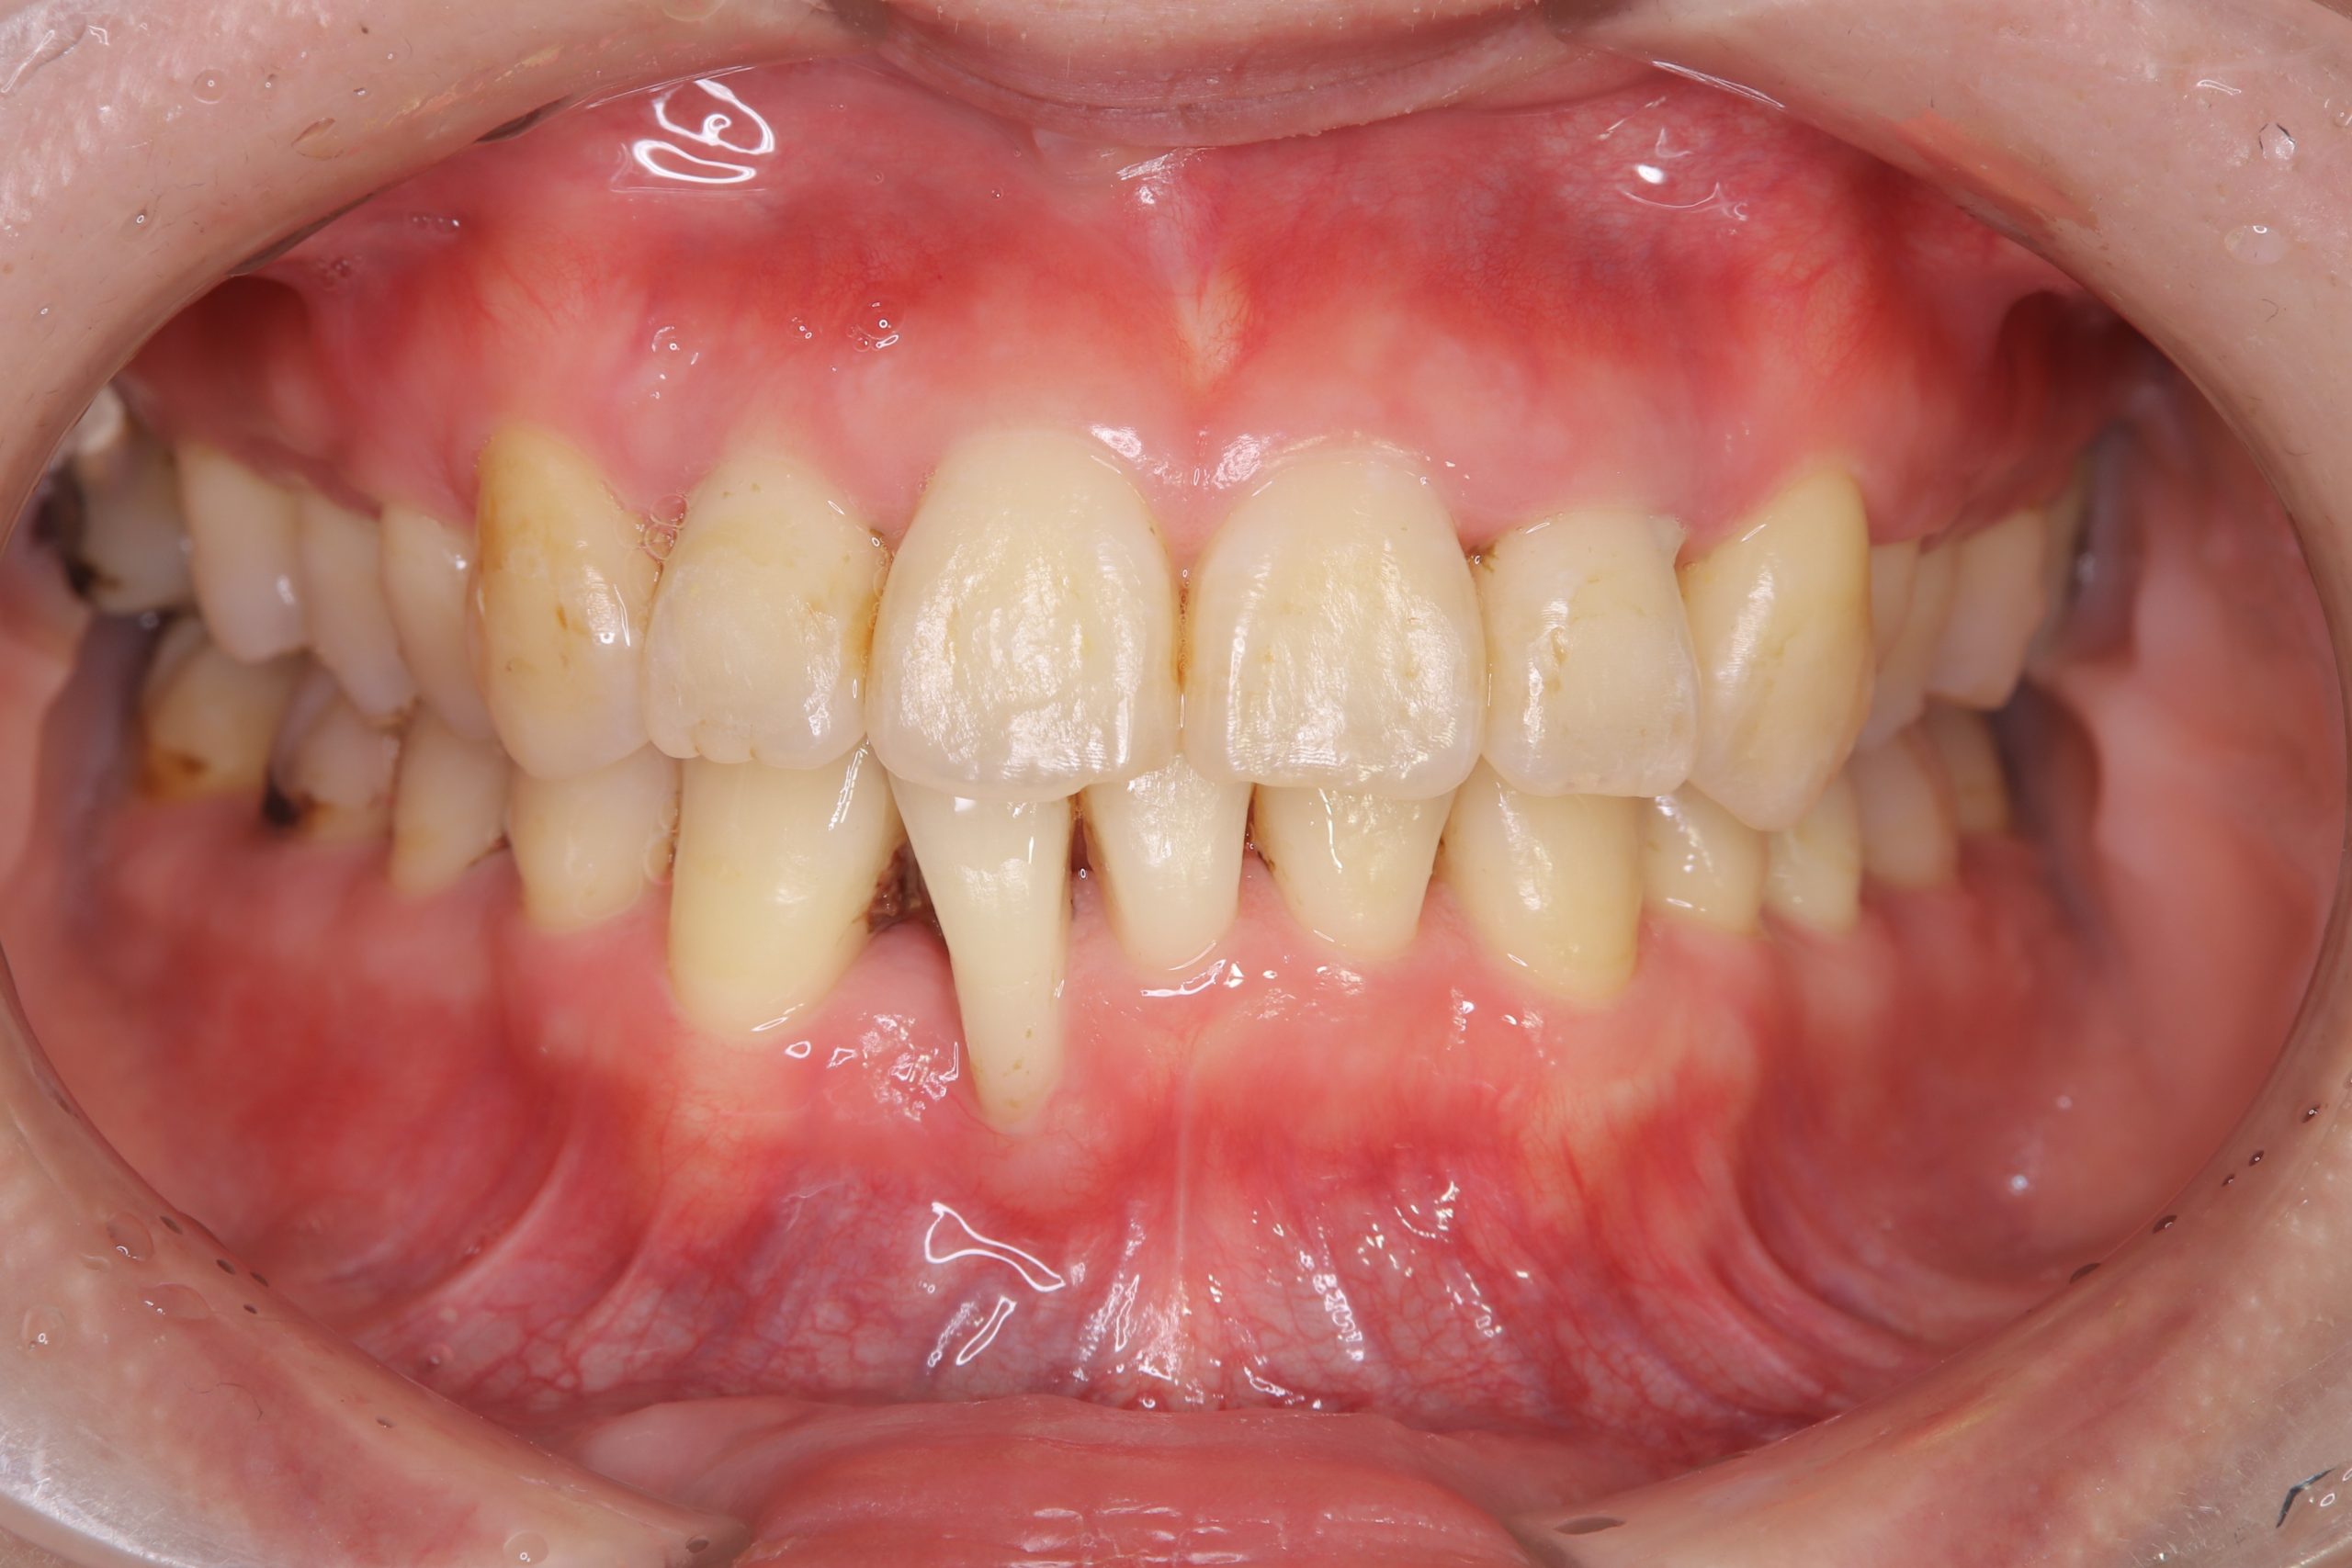

口腔内を確認すると、全体的に歯肉は炎症を起こして腫れており、下顎前歯の歯肉には著しい退縮を認めました。

歯周組織検査を行うと、30代にもかかわらず、中等度から重度の歯周ポケットを多数認めました。

① 歯肉縁下に多量の歯石が付着していることが問題であり、SRPで縁下歯石をしっかり取れば改善する可能性が高いこと

治療は、担当する歯科衛生士と連携を取りながら、SRP・むし歯治療・咬合調整・舌側に転位している右下2番(前歯)の抜歯・右下3番(犬歯)の近心スペース改善のダイレクトボンディング・ホームホワイトニング等を行いました。

現在は、SPT(メインテナンス)に移行し1年半程が経過しましたが、下の写真のように歯肉も歯も綺麗で、深い歯周ポケットもなく、良好に維持されています。